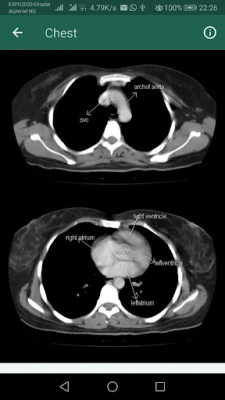

Το "Sectional Anatomy for Imaging Professionals, the App" αποτελεί τον απαραίτητο ψηφιακό σύμμαχο για κάθε επαγγελματία και σπουδαστή απεικονιστικών μεθόδων. Σχεδιασμένο για να προσφέρει μια ασυναγώνιστη οπτική εμπειρία, η εφαρμογή μετατρέπει την περίπλοκη ανατομία σε κατανοητή γνώση. Μέσα από μια καινοτόμο προσέγγιση, παρουσιάζει πλάι-πλάι πραγματικές διαγνωστικές εικόνες από μαγνητικές τομογραφίες (MRI) και αξονικές τομογραφίες (CT), μαζί με λεπτομερή ανατομικά σχέδια, φωτίζοντας τις πιο συχνά απεικονιζόμενες ανατομικές δομές του σώματος.

Με μια εκτενή συλλογή που ξεπερνά τις 1.500 εικόνες υψηλής ανάλυσης, συμπεριλαμβανομένων αυθεντικών απεικονίσεων και καθαρών γραμμικών σχεδίων, το "Sectional Anatomy for Imaging Professionals, the App" καλύπτει κάθε ανατομικό επίπεδο που συναντάται στην κλινική πράξη. Η παράλληλη απεικόνιση εικόνων και σχεδίων προσφέρει άμεση σύγκριση, ενισχύοντας την κατανόηση της θέσης και της λειτουργίας κάθε δομής. Κάθε ενότητα περιλαμβάνει σαφείς περιγραφές και ευδιάκριτες ετικέτες, επιτρέποντας την άμεση και ακριβή αναγνώριση των ανατομικών σημείων κατά τις εξετάσεις.

Αποτελώντας ένα ολοκληρωμένο βοήθημα αναφοράς, η εφαρμογή ενισχύει την ικανότητά σας να παράγετε διαγνωστικές εικόνες υψηλότερης δυνατής ποιότητας. Οι ενημερωμένοι πίνακες σύνοψης απλοποιούν την οργάνωση βασικών πληροφοριών, ενώ ειδικές εικόνες στην έναρξη κάθε κεφαλαίου κεντρίζουν το ενδιαφέρον για την επερχόμενη ύλη. Αναφορά σχέδια και αντίστοιχα επίπεδα σάρωσης εμφανίζονται δίπλα στις πραγματικές εικόνες, προσφέροντας εύκολη συσχέτιση. Να σημειωθεί ότι το "Sectional Anatomy for Imaging Professionals, the App" είναι ένα εκπαιδευτικό και αναφοράς εργαλείο, και όχι συσκευή αξονικής ή μαγνητικής τομογραφίας.